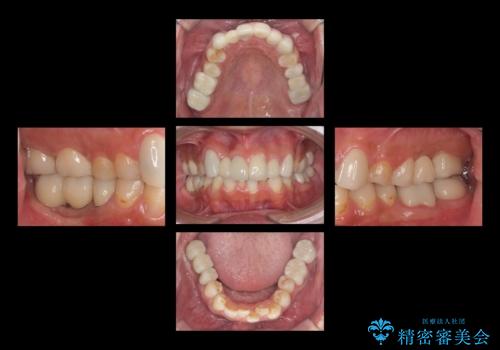

また、銀歯はすべてやり直しを行い、セラミックでやり替えを行いました。

前歯の治療を先に行い、見た目を改善した後、奥歯の治療を行いました。

途中患者様が忙しく、通院間隔が空いたため、治療の完了には時間がかかりました。